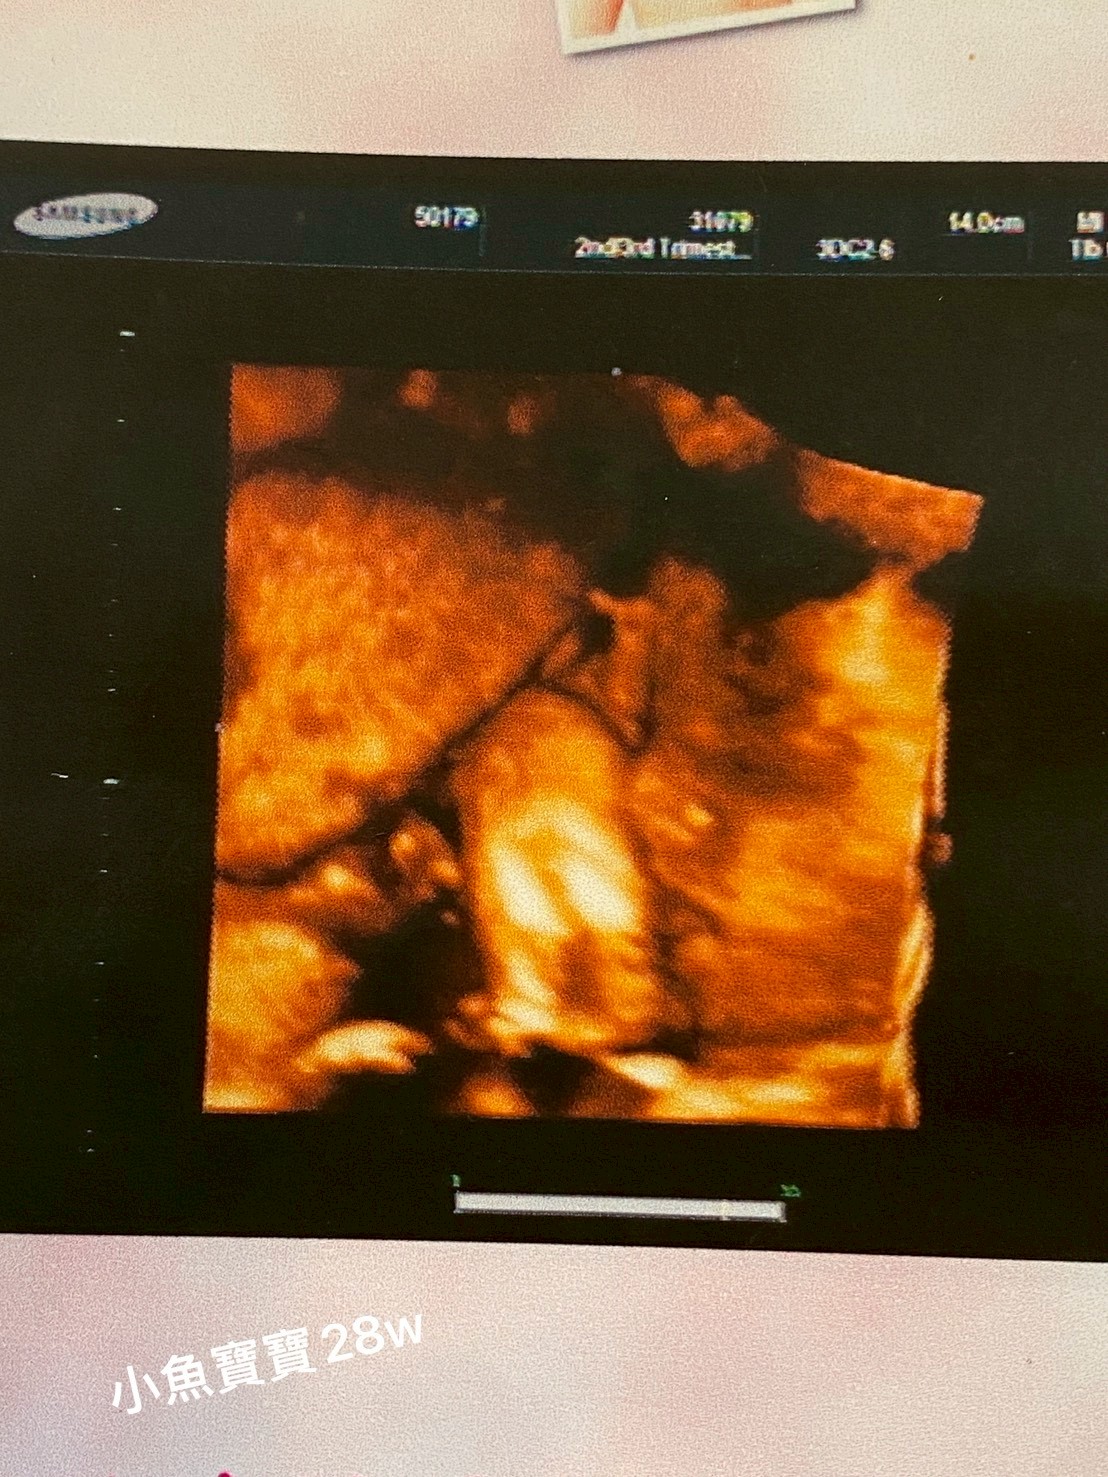

我們陪同多位媽媽前往產檢,在候診室裡一起等待、在檢查前後細心關心她們的身心狀況~

對不少媽媽而言,懷孕的過程不只是身體的變化,更伴隨著焦慮、不安與對未來的擔憂…

而有人願意在她們身旁同行,傾聽與陪伴,往往能讓她們在孤單與害怕中,重新感受到被接住、被理解或是剛離開高壓家庭的孕媽媽,拿著您們提供的生活用品時: